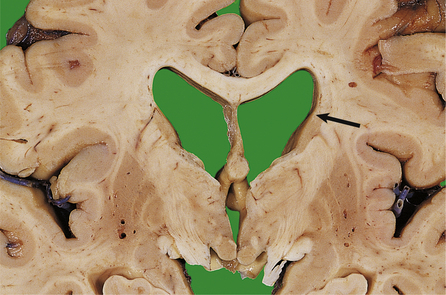

Acquired hydrocephalus can result from any lesion that obstructs the CSF pathway (Fig. 26.8). Expanding lesions in the posterior fossa are particularly prone to cause hydrocephalus, as the fourth ventricle and aqueduct are easily obstructed. Some lesions may cause intermittent obstruction, particularly colloid cysts of the third ventricle which may block the foramen of Monro. Obstructive hydrocephalus commonly results from the organisation of blood clot or inflammatory exudate in the CSF pathway following an episode of haemorrhage or meningitis (Fig. 26.9). Intermittent pressure hydrocephalus is thought to result from defective CSF absorption at the arachnoid villi.

image

Fig. 26.9 Longstanding hydrocephalus. image The lateral ventricles are very dilated and contain a prominent choroid plexus (arrow). The overlying white and grey matter are atrophic. Fibrous adhesions are present in the ventricles posteriorly, suggestive of previous infection. image In the same case, the cerebral aqueduct in the midbrain is completely obliterated by glial tissue as a consequence of a previous viral infection (arrow). This has resulted in obstructive hydrocephalus.

The complications of hydrocephalus can be averted or relieved by the insertion of a ventricular shunt with a one-way valve system to drain CSF into the peritoneum. Untreated patients may suffer irreversible brain damage (Fig. 26.9). Ventricular shunts often need to be replaced in growing children and are prone to become infected with low-virulence bacteria, for example Staphylococcus epidermidis. Infection may result in shunt blockage and exacerbation of symptoms attributable to raised intracranial pressure.